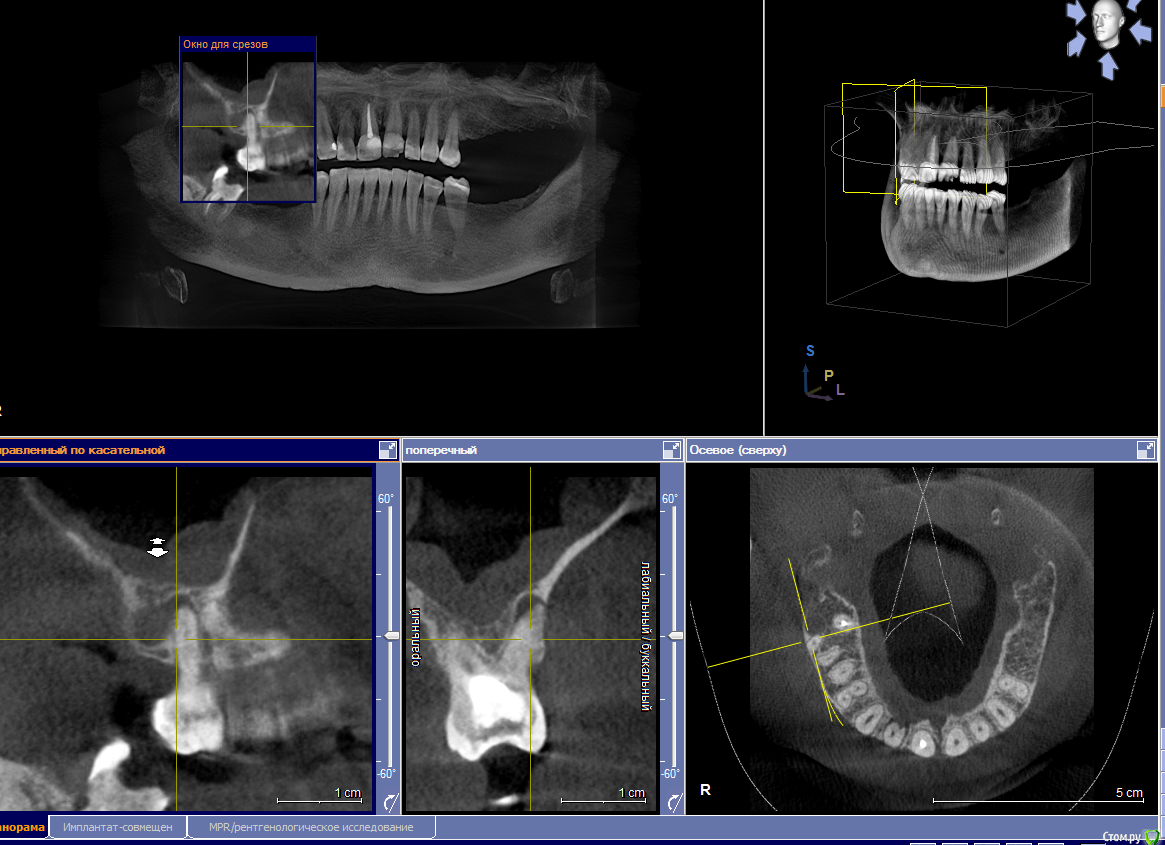

elesilchenko@yandex.ru Опубликовано 18 октября, 2016 Поделиться Опубликовано 18 октября, 2016 Здравствуйте! Подскажите, пожалуйста, возможна ли дентальная имплантация на НЧ без применения костной пластики? И возможно ли спасти зубы с кистами на ВЧ ?Результаты КТ: http://files.mail.ru/1F70A64348084F03ACC722DA9E76BD2B Ссылка на комментарий

elesilchenko@yandex.ru Опубликовано 18 октября, 2016 Автор Поделиться Опубликовано 18 октября, 2016 Добрый вечер! Я в процессе выбора, кто предлагает базальную имплантацию внизу (ВЧ я пока не рассматриваю к имплантации) , кто съемные протезы это на НЧ. По поводу ВЧ тоже разные мнения: 1. Можно полечить, т.к. проблемы с эндодонтией 16 и 12, где небольшой воспалительный процесс.2. 16 удалить, 12 попытаться полечить. Сунус-лифтинга и костной пластики боюсь. Ссылка на комментарий

IvanK Опубликовано 18 октября, 2016 Поделиться Опубликовано 18 октября, 2016 Судя по скудной информации из скриншотов:кости , скорее всего, будет достаточно Вам нужно найти Врача, которому доверяете и довериться) Сходите на пару-тройку очных консультаций Ссылка на комментарий